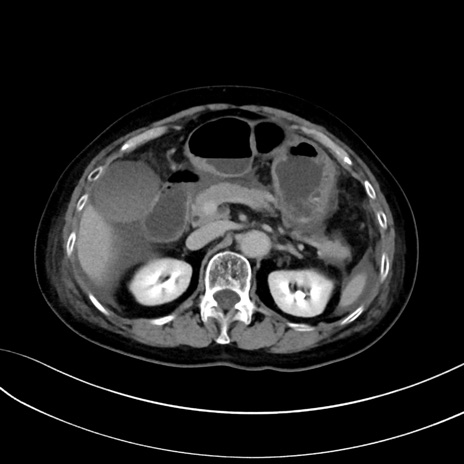

症例13 CT(横断像)1日半後